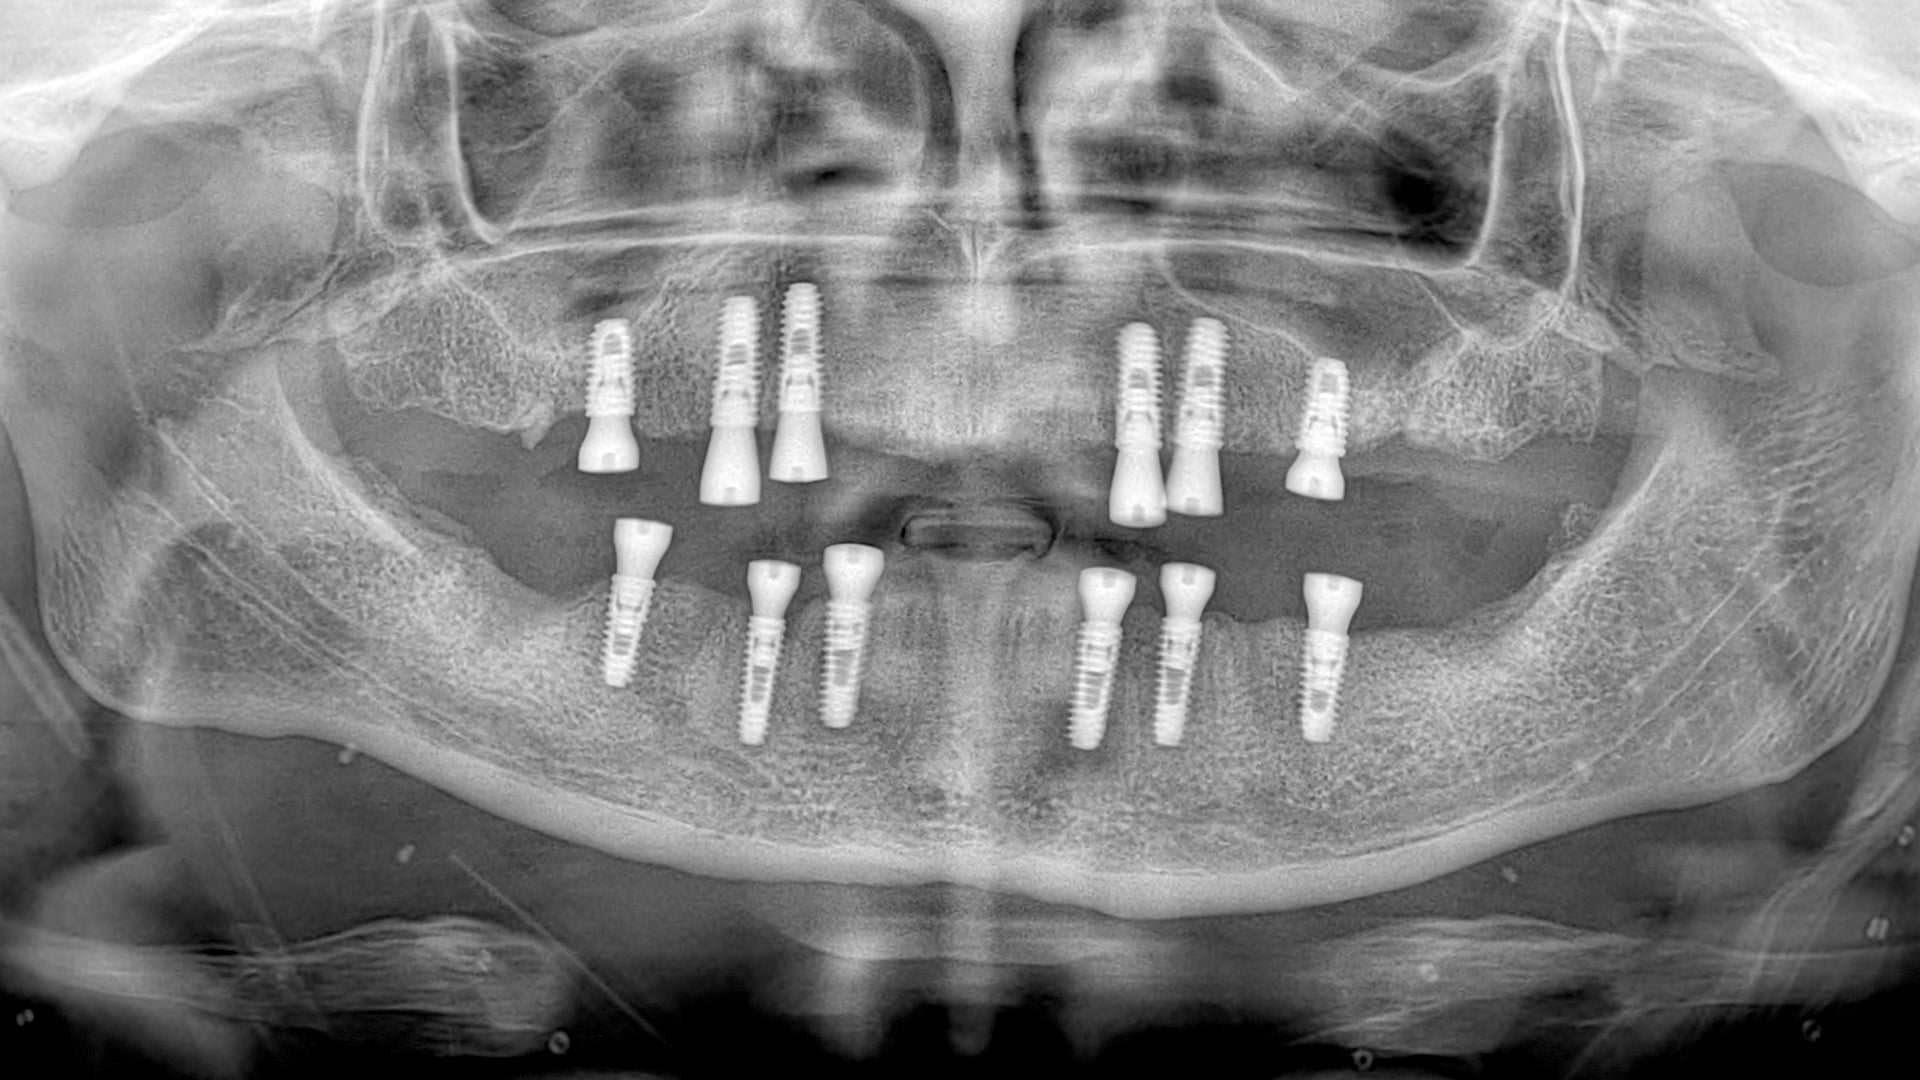

Dental implants are artificial tooth root-like materials made of titanium. They have various applications in cases where there is sufficient bone in the empty space left by a missing tooth. These materials are placed into the bone and allowed to integrate with it after implantation. Once the implant has fused with the bone, fixed or removable prosthetic restorations can be created for the superstructures.

In some cases, implants can be placed during the same session as tooth extraction. Immediate implant placement, which has become a common treatment method in recent years, is preferred when there is no infection during the extraction session.

Immediate implants placed after extraction can have prosthetic restorations applied during the same session. This approach is often chosen in the anterior region and in cases where the aesthetics of the smile are affected.

After a tooth extraction, the height of the bone gradually decreases, and the sinus cavities descend downward. After a long period of tooth loss, it becomes impossible to apply implants in that area. In such cases, a procedure called “Sinus Lift” is performed. This procedure aims to increase the volume of the bone. With a special surgical technique, the sagging sinus cavities are filled with bone graft material, pushing them upward. This allows for the placement of implants in the edentulous areas. The goal of this procedure is to create sufficient volume for the length and width of the implant to be placed into the bone.

This procedure can be performed under local anesthesia or general anesthesia. After 6 months, the formation of healthy bone tissue is expected. Then, the implants are placed. To be able to place the implants in the same session, there needs to be at least 4mm of bone in the area.